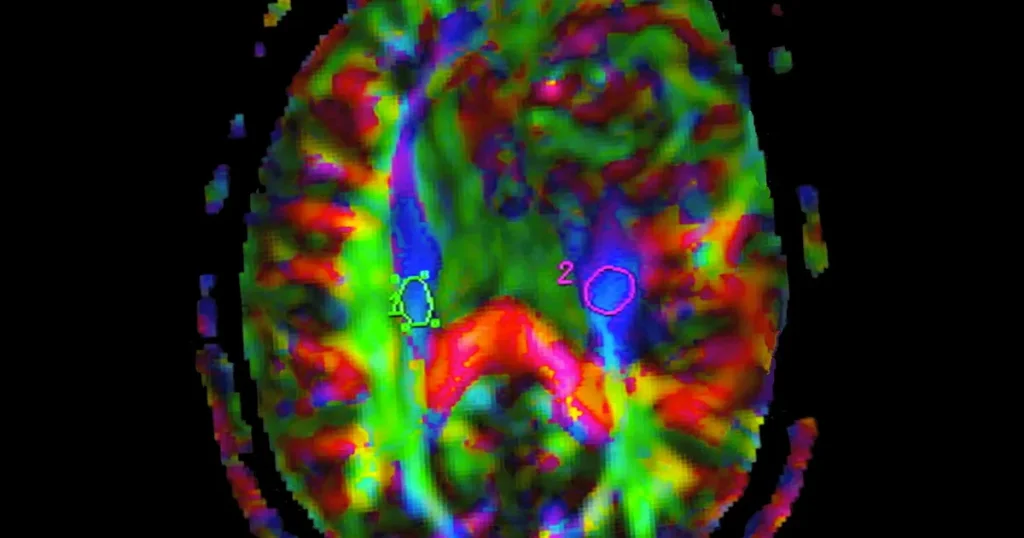

I en banbrytande studie som nyligen publicerades i tidskriften Nature Communications presenterar forskarlaget en möjlig lösning på detta problem. Undersökningen omfattade 45 patienter med glioblastom (astrocytom grad IV), en särskilt aggressiv form av hjärntumör med hög återfallsrisk och generellt dålig prognos.

Patienterna delades slumpmässigt in i två behandlingsgrupper. Den första gruppen erhöll konventionell behandling bestående av kirurgiskt ingrepp följt av checkpointhämmaren pembrolizumab. Den andra gruppen behandlades med en laserteknik kallad LITT (Laser Interstitial Thermal Therapy) följt av samma läkemedel.

Forskarna tror att laserbehandlingens framgång beror på två huvudsakliga faktorer. Tidigare studier har visat att LITT gör blod-hjärnbarriären mer genomsläpplig under cirka fyra veckor, vilket sannolikt möjliggör för läkemedlet att nå tumören mer effektivt. Dessutom reducerar lasern tumörmassan genom att framkalla så kallad immunogen celldöd, vilket frigör tumörantigen som aktiverar immunförsvarets T-celler.